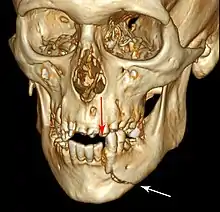

Computed tomography is the most sensitive and specific of the imaging techniques. The facial bones can be visualized as slices through the skeletal in either the axial, coronal or sagittal planes. Images can be reconstructed into a 3-dimensional view, to give a better sense of the displacement of various fragments. 3D reconstruction, however, can mask smaller fractures owing to volume averaging, scatter artifact and surrounding structures simply blocking the view of underlying areas.

3D CT reconstruction of mandible fracture, white arrow marks fracture, red arrow marks moderate displacement and open bite